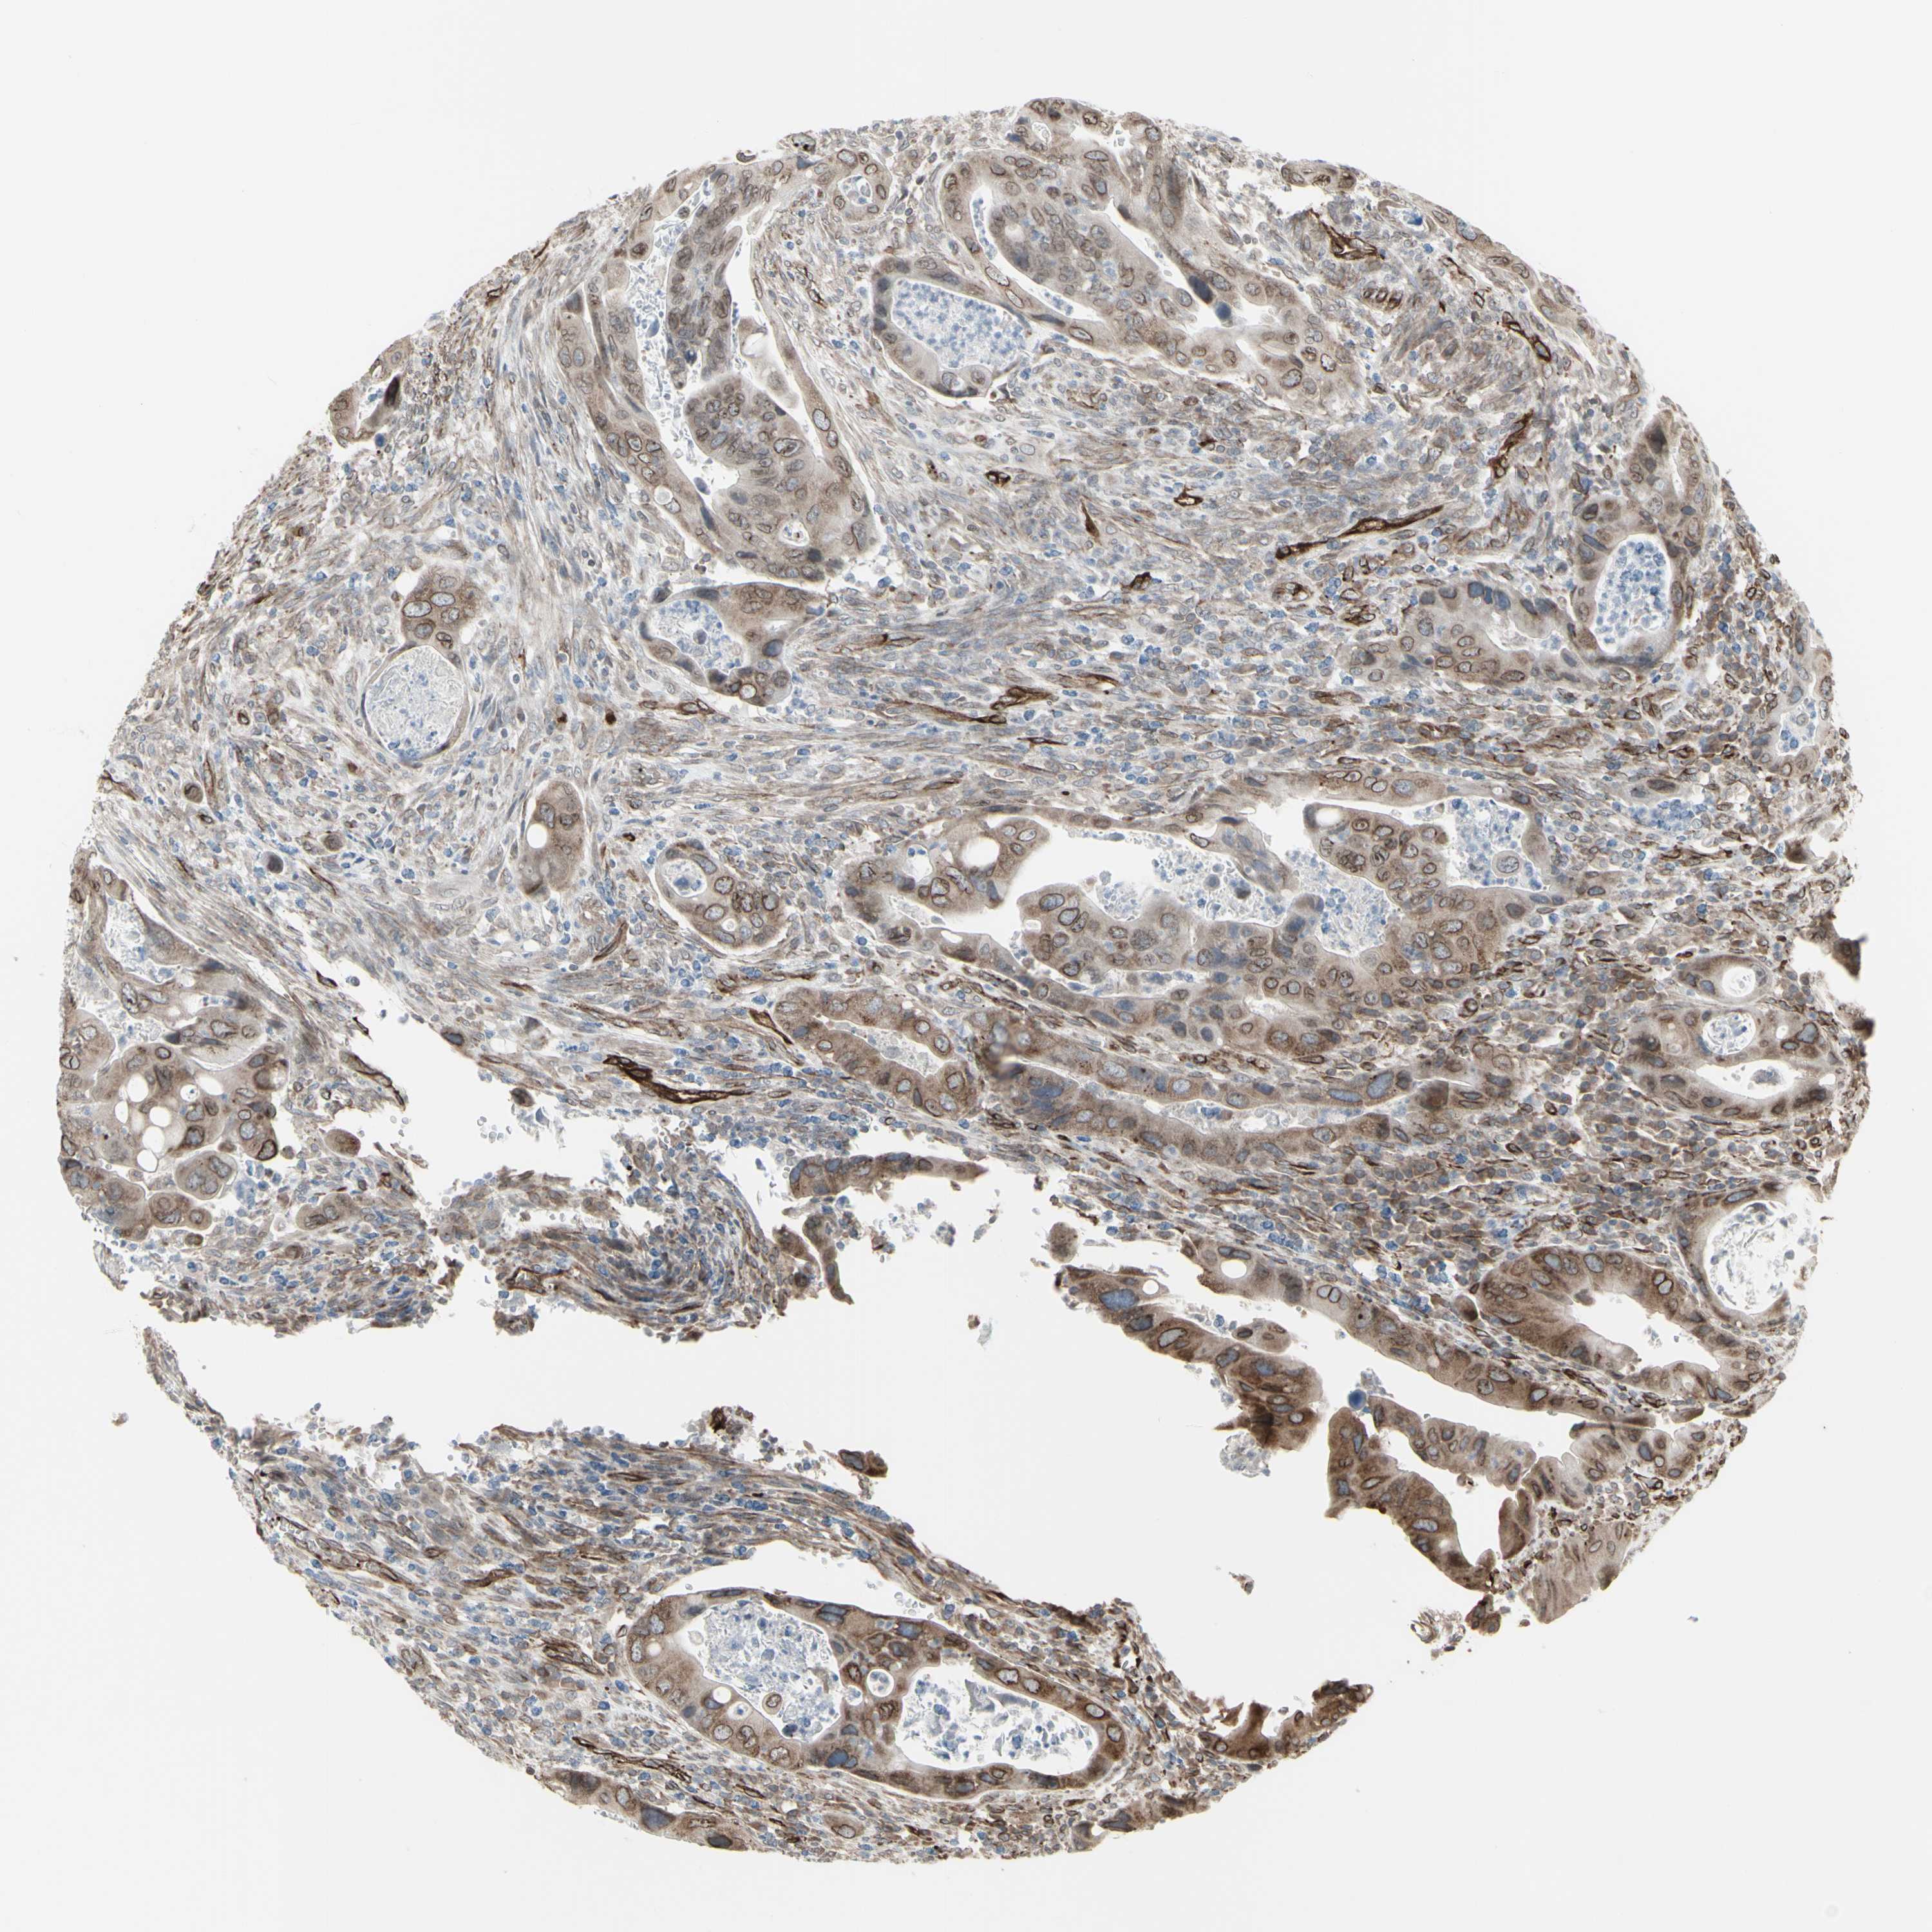

COLON ADENOCARCINOMA (VALIDATION) - Interactive survival scatter ploti

DTX3L is not prognostic in Colon Adenocarcinoma (validation)

Average pTPM 72.2

Number of samples 486